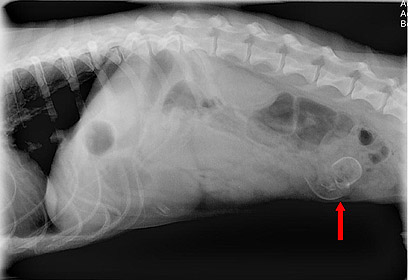

פה גדול: מה הסתתר בבטן של הכלב קולומבו?

קולומבו, כלב מגזע באסט-האונד, בעל חיבה מסוכנת לבליעת גרביים ומזון,

שוב הדאיג את בעליו. בעקבות הקאות וחוסר תיאבון, הוא הובהל לטיפול וטרינרי.

לא תאמינו מה גילו לו בבטן..